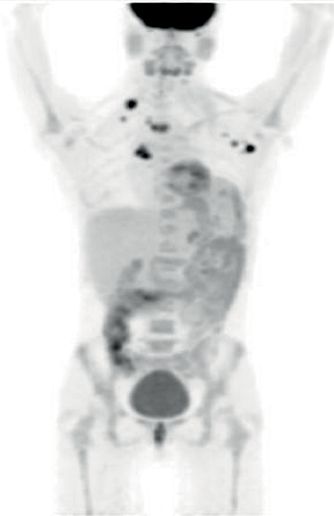

患者三:IRF2BP2-NTRK1融合非小细胞肺癌的持久反应

31岁女性被诊断患有IV期NSCLC腺癌,颈部左侧,腋窝和右乳内淋巴结转移,对腹部和锁骨上窝的放射治疗后,患者出现周围神经病变,颈部疼痛和粘膜炎,对所有先前的全身治疗均无反应,包括顺铂,培美曲塞和多西紫杉醇。

FoundationOne检测具有NTRK融合基因,接受larotrectinib 100 mg BID,在第56天确认完全反应,所有症状完全消除,反应持续时间> 20.27个月,患者仍在接受治疗,未报告严重不良事件。